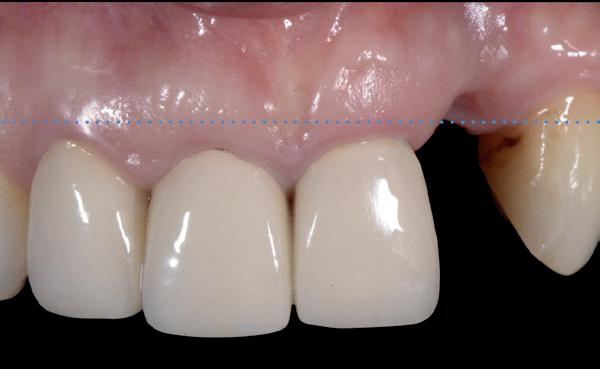

De flap en graft worden met poly-propelene 6.0 hechtingen gefixeerd. De tijdelijke reconstructie wordt herplaatst (foto 17-20).

Na 4-6 weken kan het aangebrachte healing abutment worden vervangen door een tijdelijk abutment. Deze wordt aan de kunststof reconstructie verbonden om zo de gingiva ter plaatse van de 22 te vormen. Zo lijkt het of er geen implantaat maar nog steeds een wortel aanwezig is, wat het esthetisch eindresultaat ten goede zal komen (foto 21-23). Vanaf 4-6 maanden ziet het weefsel er gezond uit. Nu kan met de uiteindelijke restauratiefase worden gestart (foto 24 en 25).